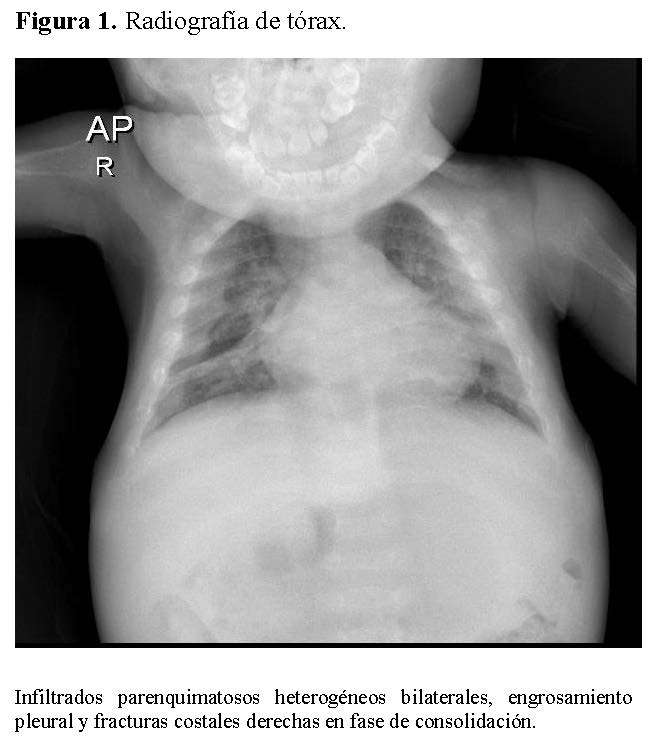

La radiografía de tórax mostró infiltrados parenquimatosos heterogéneos bilaterales, engrosamiento pleural y fracturas costales derechas en fase de consolidación (Figura 1). Las radiografías de huesos largos evidenciaron osteopenia severa, reacción perióstica y múltiples fracturas patológicas, incluyendo húmero derecho e izquierdo, cúbito derecho y fémur derecho (Figuras 2 y 3).